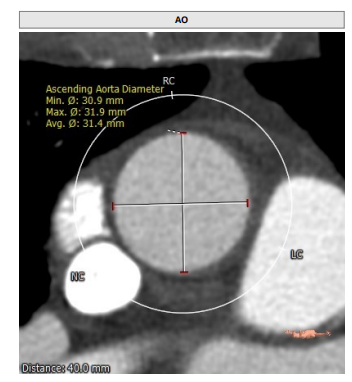

近日,珠海市人民医院心血管内科姜小飞主任带领瓣膜介入团队,在超声科张恒主任团队、麻醉科刘贵德主任团队以及影像科等兄弟科室全力配合下,成功为一位主动脉瓣重度狭窄合并轻度返流的患者完成经导管主动脉瓣置换术(TAVR)。该病例极具挑战性,病人整体结构小,瓣环16.9mm,左室流出道16.7mm,窦管结合部23.9mm,升主动脉31.4mm。在姜小飞主任团队前期充足的准备,通过术前评估,制定手术策略和预案,充分对比目前可以使用的瓣膜系统,最后应用VenusA-Plus挑战成功了三叶式“4小”高难度TAVR病例。

STJ:23.9mm;升主动脉:31.4mm

患者为三叶瓣,左右、右无疑似粘连,瓣叶明显增厚,轻度钙化。右冠高度10.9mm,左冠高度9.5mm,冠脉高度均较低。法式窦小,心脏角度不大,左室大小可,升主动脉未见明显增宽,病人整体结构小,瓣环仅有16.9mm,左室流出道16.7mm,窦管结合部23.9mm,升主动脉31.4mm。选择右股作为主入路。